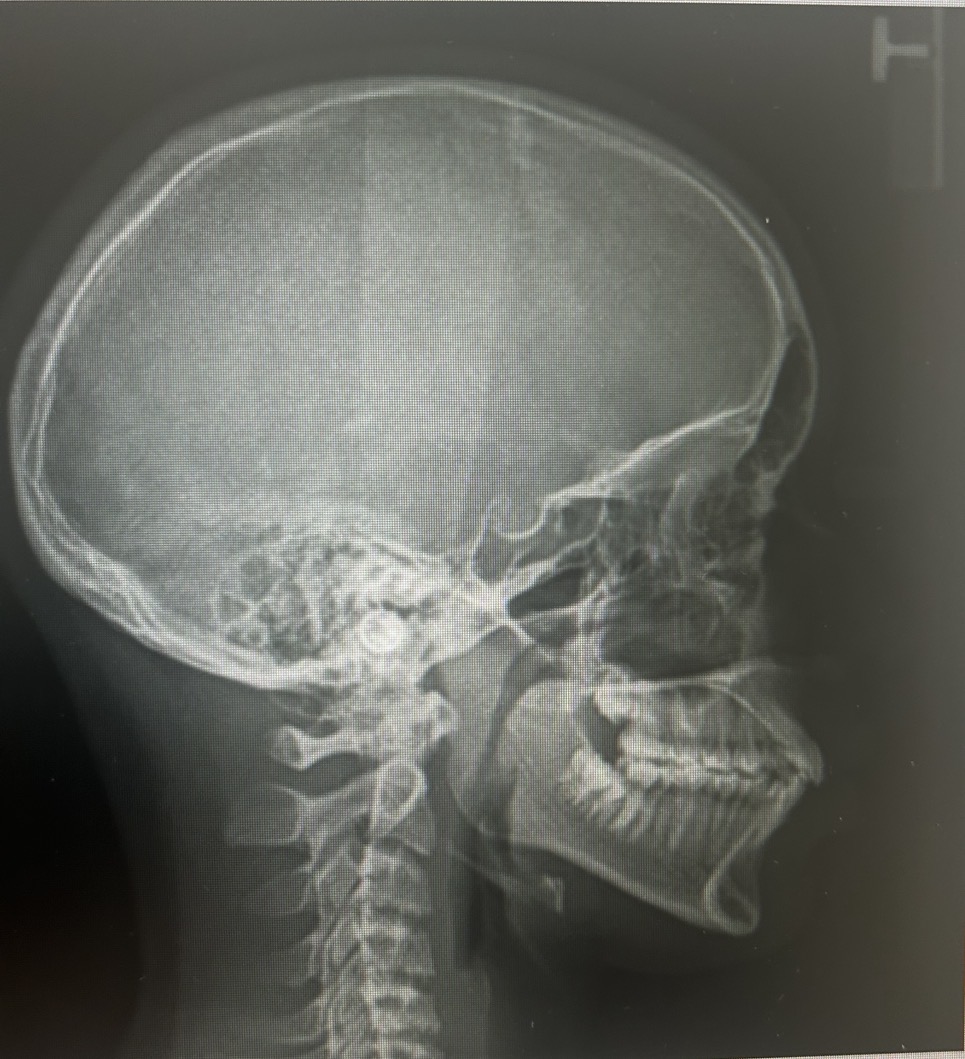

Here are some photos that were taken at the orthodntics. lmk what yall think